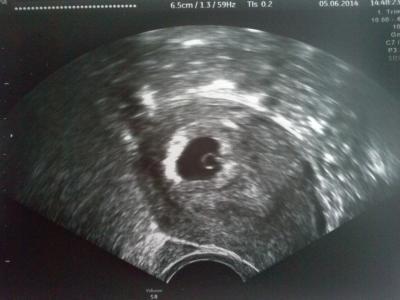

Man sieht den Dottersack und sogar ein bißchen schon die embryonale Anlage. Er meinte sogar, schon etwas zucken zu sehen (Herzchen), hat sich da aber nicht festgelegt.

Alles ist super, wir freuen uns und sind froh, dass alles passt, ABER - ich hoffe, ihr schimpft mich nicht - es gibt etwas, was mich ein bißchen stört und zwar hat er die embryonale Anlage vermessen und sagte etwas von 0,7 mm! Müsste das in der 6. Woche nicht mehr sein? Oder meinte er vielleicht das, was er zu diesem Zeitpunkt halt vom Embryo vermessen kann? Kann es sein, dass es eh schon ein paar mm hat, aber er davon nur 0,7 vermessen konnte (es sitzt am Rand gleich rechts vom Dottersack). Ich stell euch mal ein Bild rein. Was meint ihr?

Bei 6+3 war mein Flips 4,4 mm groß. Also das passt doch, würde ich sagen. Und wenn sie so klein sind, kommt es leicht zu Differenzen. Aber Glückwunsch zum Herzschlag LG